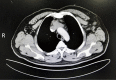

Figure 1

Representative image of contrast-enhanced tomography of the invasive thymoma, which invading superior vena cava (Case 15, Type B3, Stage IVA).